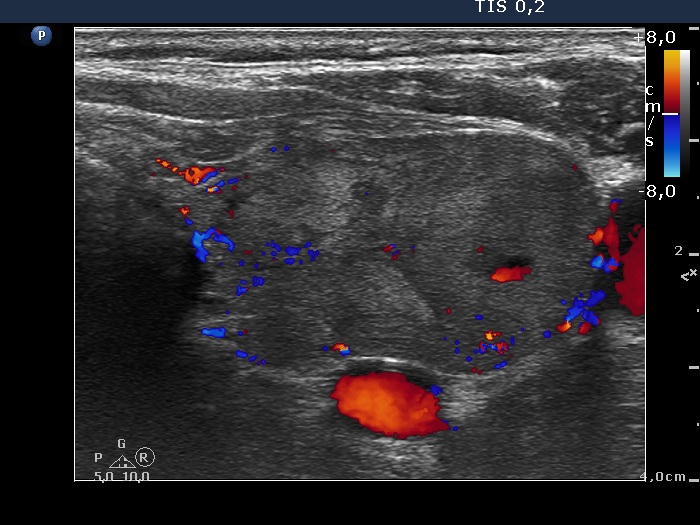

Right lobe, longitudinal scan

Left lobe, transverse scan, color Doppler mode. The vascularization is not specific.